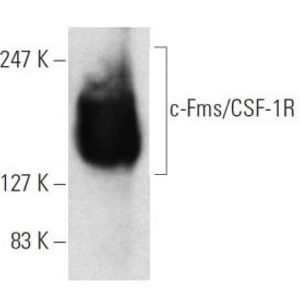

JUL 28, 2025Drug Discovery & DevelopmentOne lab technique that has been around since what feels like the dawn of time is Western blotting, and it doesn&r ...